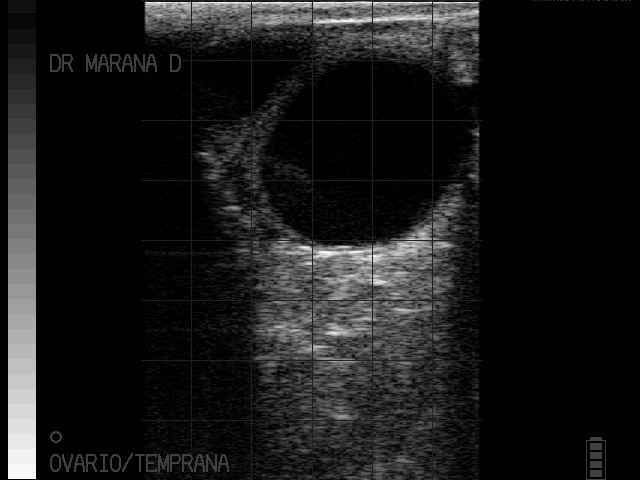

Quiste

imagenes cortesia:

MVZ MsC David Maraña Peña Especialista en Reproducción Bovina